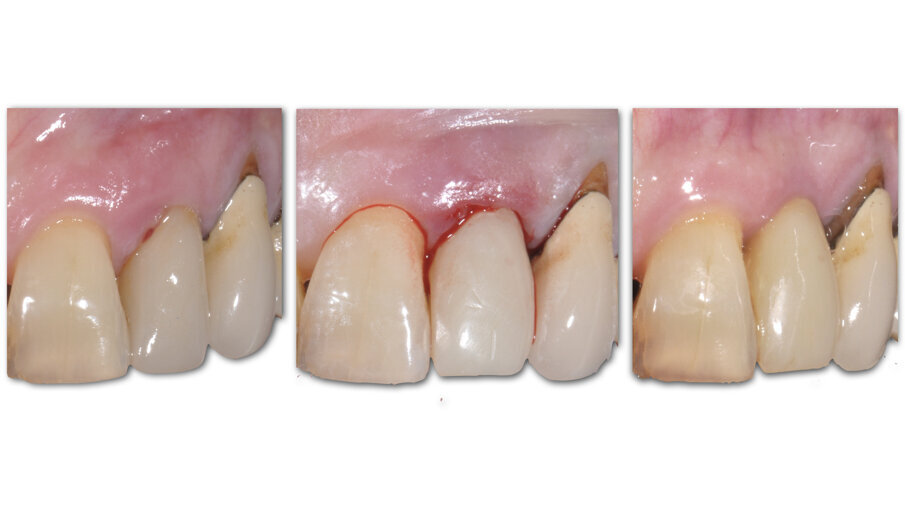

A 7 giorni è stato eseguito un controllo per verificare lo stato dei tessuti gengivali e continuare a motivare la paziente riguardo all’esclusione dai carichi masticatori (Fig. 9). A 90 giorni è stato rimosso il provvisorio per procedere al restauro ceramico. Nonostante la superficie SLActive preveda un accorciamento dei tempi di integrazione, è stato deciso un tempo di attesa convenzionale per accertarsi della stabilità dei tessuti molli perimplantari (Figg. 10-12). È stato eseguito un workflow digitale a partire dall’impronta ottica, fino alla realizzazione di un restauro in Zirconia precolorata e stratificata vestibolare (Dental Direkt 1200 e Creation ZI-CT) su base titanio (Figg. 13, 14). Il restauro è stato consegnato mediante avvitamento a controllo di torque secondo le indicazioni della casa produttrice (Figg. 15, 16).

Fig. 10_Aspetto clinico a 90 giorni.

Fig. 11_Condizionamento dei tessuti molli.

Fig. 12_Confronto tra la situazione iniziale, quella post-chirurgica e quella al termine del periodo provvisorio.